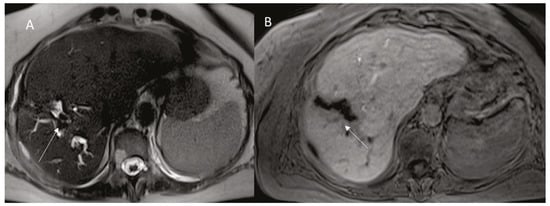

8. Fistulae